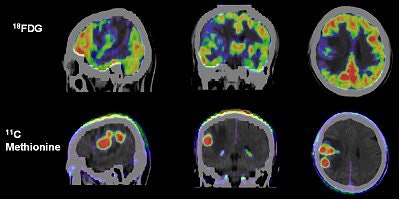

![]() |

| Primary glioma imaged on FDG-PET and 11C-methionine PET, revealing tumor glucose utilization and protein synthesis respectively. Image courtesy of Siemens Medical Solutions and Huashan Hospital, Shanghai. |